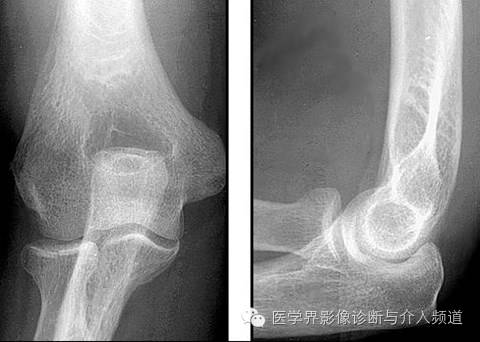

17、Nuresmaid’s Elbow

桡骨小头脱位。受伤机制为过度牵拉前臂,如家长拉着小孩上台阶。X线表现为桡骨骨干中轴线不经过肱骨小头骨骺中心。